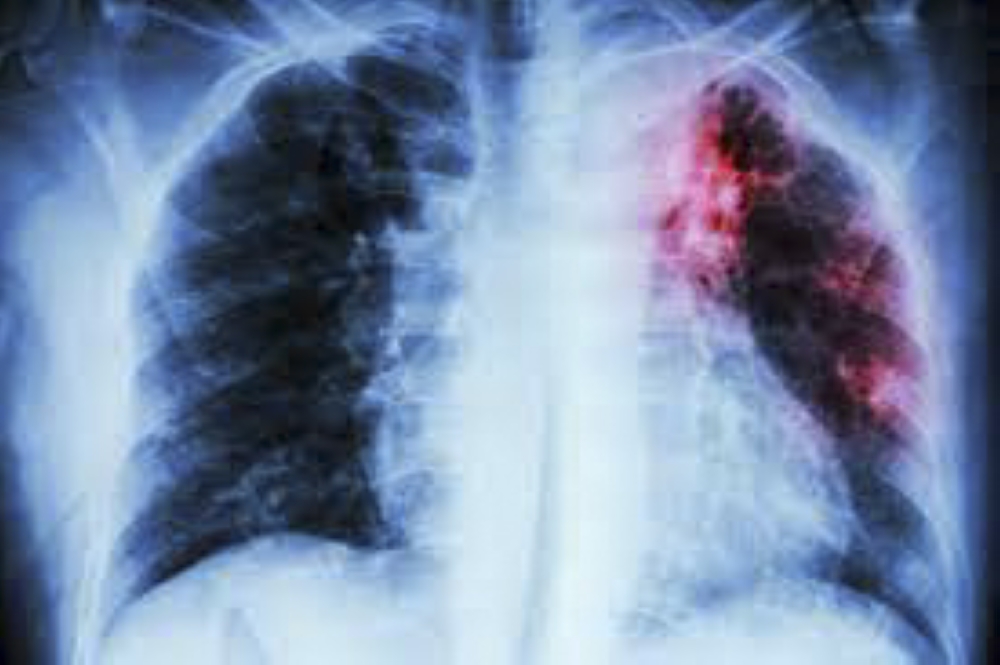

U.S. President Trump’s spending freeze on foreign aid marks a significant challenge for the international development community, and many experts warn that diseases will surge. During this time of uncertainty about the future role of the world’s biggest donor, the Global Fund stands as a beacon of hope. Since the beginning of the millennium, the Geneva-based multilateral organisation has been fighting one of humanity’s oldest scourges, infectious disease—and specifically the three big killers, malaria, HIV, and tuberculosis. Through targeted funding and innovative strategies, the Global Fund has made significant breakthroughs against malaria and HIV. Now, the time is ripe to sharpen its focus on tuberculosis. Nearly one-third of the Global Fund’s 2023-2025 allocations have gone to the fight against malaria, amounting to some $4.17 billion. These funds have supported large-scale distribution of insecticide-treated bed nets and rapid diagnostic tests, drastically reducing transmission rates. Countries like Rwanda and Zambia have seen remarkable declines in malaria cases and deaths. For HIV, the Global Fund is spending $6.48 billion, amounting to nearly half its allocations. In the past decade, the Fund has facilitated access to antiretroviral therapy (ART) for millions, helping to transform HIV from a fatal disease into a manageable chronic condition. By promoting education and prevention, particularly in vulnerable communities, the Global Fund has empowered individuals to take control of their health. Together, these efforts have saved countless lives and advanced global health security. But it is now time to reassess. Tuberculosis prevention and control has been allocated $2.4 billion or just 18% of the Global Fund allocations budget—and has received less than HIV or malaria in every year since the Global Fund was created. But tuberculosis now kills more people than HIV and malaria together. It is by far the world’s leading infectious disease killer. Not only do malaria and HIV receive far more resources from the Global Fund than tuberculosis, but they also get much more global publicity and media coverage. Tuberculosis, in comparison, is a neglected, forgotten, and often ignored disease. To understand why, we need to look at the history of tuberculosis. For people in the rich world today, the disease is little more than a dim memory of a bygone era. But back then, tuberculosis was frightful. In the 1800s it brought a tsunami of death, killing one-in-four across Europe and the US. For most of the 1800s, New York City’s tuberculosis death rate alone was higher than the total death rate in the city today. Across the 1800s, tuberculosis was a much bigger killer than the recent global Covid pandemic managed even in its worst year. Over the past two centuries, tuberculosis has likely killed one billion people. Yet, almost like magic, tuberculosis has disappeared in the rich world. Antibiotics and a childhood vaccine, combined with better living standards, rudimentary public health measures, and subsequent treatment breakthroughs, mean that the disease has been largely eradicated in wealthier countries. But mostly, tuberculosis has lost the attention of the rich world. Not so for the world’s poorer half, where tuberculosis still claims nearly 1.3 million lives every year. For comparison, that is greater than the combined death toll of HIV/AIDS (630,000) and malaria (619,000). For more than half a century, we have known how to cure tuberculosis. Yet, it persists and kills a record number of people in the poorer part of the world. It mostly kills adults in their prime, leaving children without parents. Tuberculosis has become an illness of poverty. It spreads when people live in close quarters and are unable to afford space, and it thrives among populations who cannot afford basic healthcare and services. The most vulnerable, living in slums, migrant areas, mining towns and prisons are also the most voiceless. Tuberculosis has gone from risking the lives of all to just killing those that nobody cares enough about. Needless to say, this shouldn’t be the way. We know how to defeat the disease. It would take surprisingly few resources. Research for the Copenhagen Consensus think-tank shows that additional expenditure of $6.2 billion annually could save about a million lives a year over coming decades, making this one of the very best possible development policies. This spending would enable much broader diagnosis to end onwards infections and ensure most tuberculosis patients stay on medication, reducing deaths by 90 percent by 2030. The benefits, including the reduction in death and disease, outweigh the healthcare and time costs by 46 to 1. The Global Fund is in the middle of its three-year replenishment cycle, when it asks the world for more resources. The world needs to be generous because the Global Fund has shown that it is one of the very best ways to achieve good in the world. And the Global Fund – as well as development agencies everywhere – need to focus more on the illness that is claiming the most lives, and where investment can deliver an astonishing return on investment. Dr Aaron Motsoaledi is South Africa's Minister of Health. Dr Bjorn Lomborg is president of the Copenhagen Consensus.